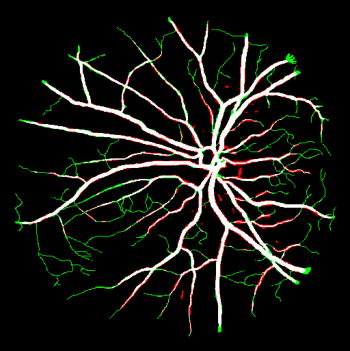

Vessel segmentation is an essential task in many clinical applications. Although supervised methods have achieved state-of-art performance, acquiring expert annotation is laborious and mostly limited for two-dimensional datasets with a small sample size. On the contrary, unsupervised methods rely on handcrafted features to detect tube-like structures such as vessels. However, those methods require complex pipelines involving several hyper-parameters and design choices rendering the procedure sensitive, dataset-specific, and not generalizable. We propose a self-supervised method with a limited number of hyper-parameters that is generalizable across modalities. Our method uses tube-like structure properties, such as connectivity, profile consistency, and bifurcation, to introduce inductive bias into a learning algorithm. To model those properties, we generate a vector field that we refer to as a flow. Our experiments on various public datasets in 2D and 3D show that our method performs better than unsupervised methods while learning useful transferable features from unlabeled data. Unlike generic self-supervised methods, the learned features learn vessel-relevant features that are transferable for supervised approaches, which is essential when the number of annotated data is limited.